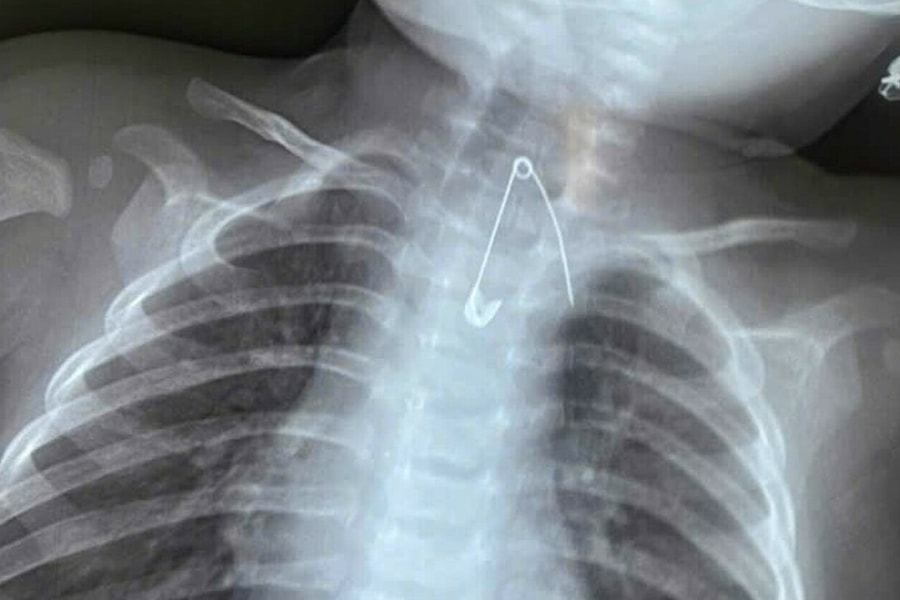

Chiếc kim băng găm vào thực quản bé 7 tháng tuổi

Bé trai 7 tháng tuổi sốt, ho kéo dài hai ngày, bác sĩ phát hiện chiếc kim băng mắc ở thực quản bé, sát động mạch chủ.